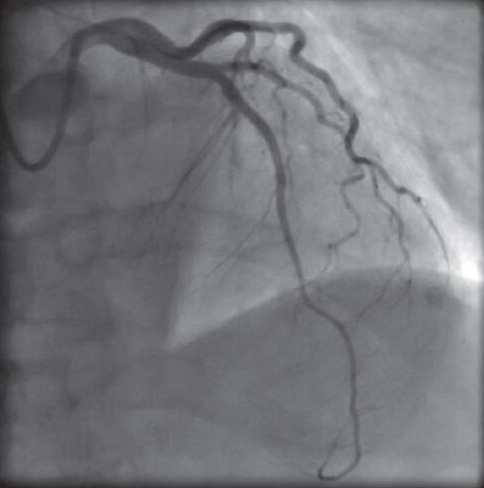

这就和预想的不一样了,说好的动脉粥样斑块破裂的,说好的冠脉狭窄的,这画风转变的有点突然啊!抽吸后前降支血流恢复至TIMI3级(图6),未见冠脉狭窄,患者胸痛症状缓解,未行支架植入术。

图6 抽吸后前降支血流恢复正常